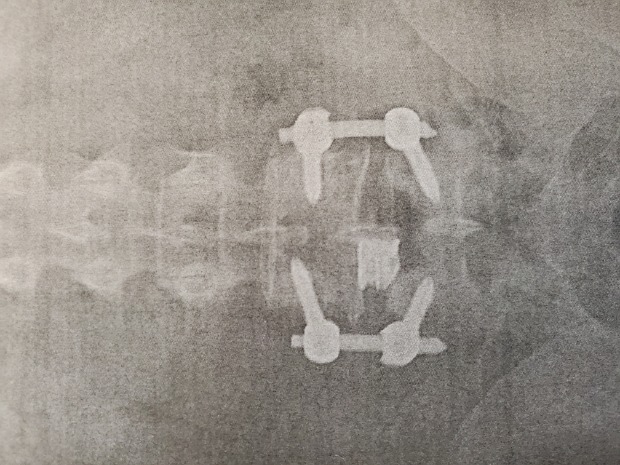

I went and saw the doctor yesterday, the fusion is taking well the recovery is going good, my L4 and L5 went from being about 35% out of alignment to back to alignment, the doctor was afraid that he might not be able to get it back to less than 15% due to how bat it was, but look at those sexy vertebrates now.

Post Image